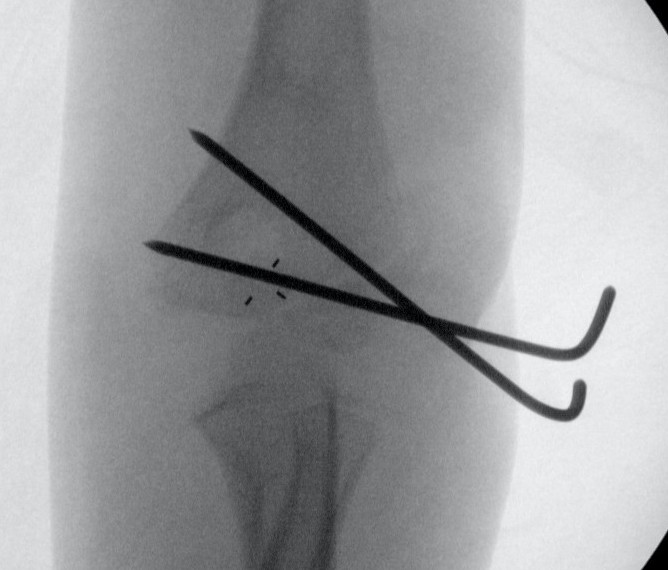

Closed reduction and percutaneous K wires

Indications

- residual displacement < 2 mm

- no rotation

- confirm joint surface anatomically reduced (arthrogram)

Technique

- reduce by extension and varus

- pronation uses flexor mass to pull lateral condyle forward

- percutaneous K wire